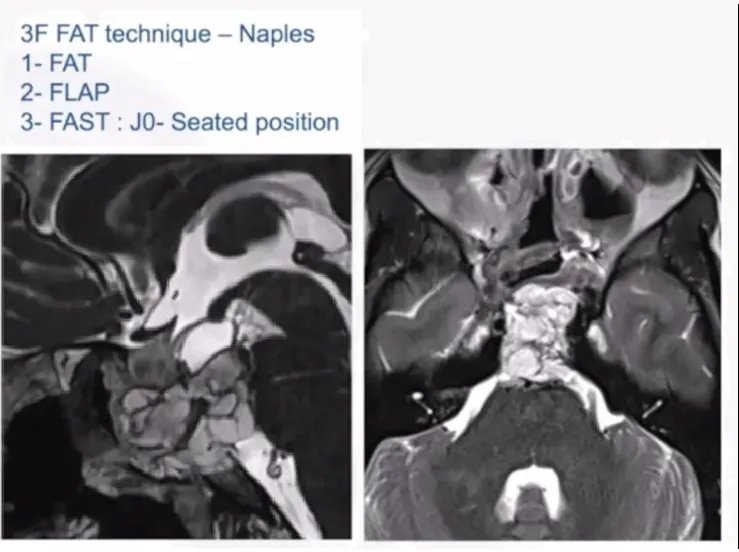

3F脂肪技术-Naples,ITALY

1、脂肪填充

2、皮瓣闭合

3、尽可能快地保持患者直立的姿势,以降低颅内压

对于硬膜的闭合,福教授采用了各种技术,Multilayer、Gasket-seal,用过缝合线以及各种各样的产品(Multilayer、Gasket Seal、Sutures、Duraseal、Fat、Glue、Bone)。在闭合脑脊液漏的问题上需要足够关注颅内压。如果不能很好的控制颅内压,颅内压升高,需想办法进行闭合,CFS会迫使他闭合,所以控制颅内压,无论是用腰椎管引流,还是用腰椎管上的分流管,或是用位置来控制都是重要的。在大多数案例中,使用了脂肪型鼻中隔皮瓣。术后重点控制颅内压,以降低脑脊液漏的发生率,福教授认为这是术后避免脑脊液漏较重要的方面之一。